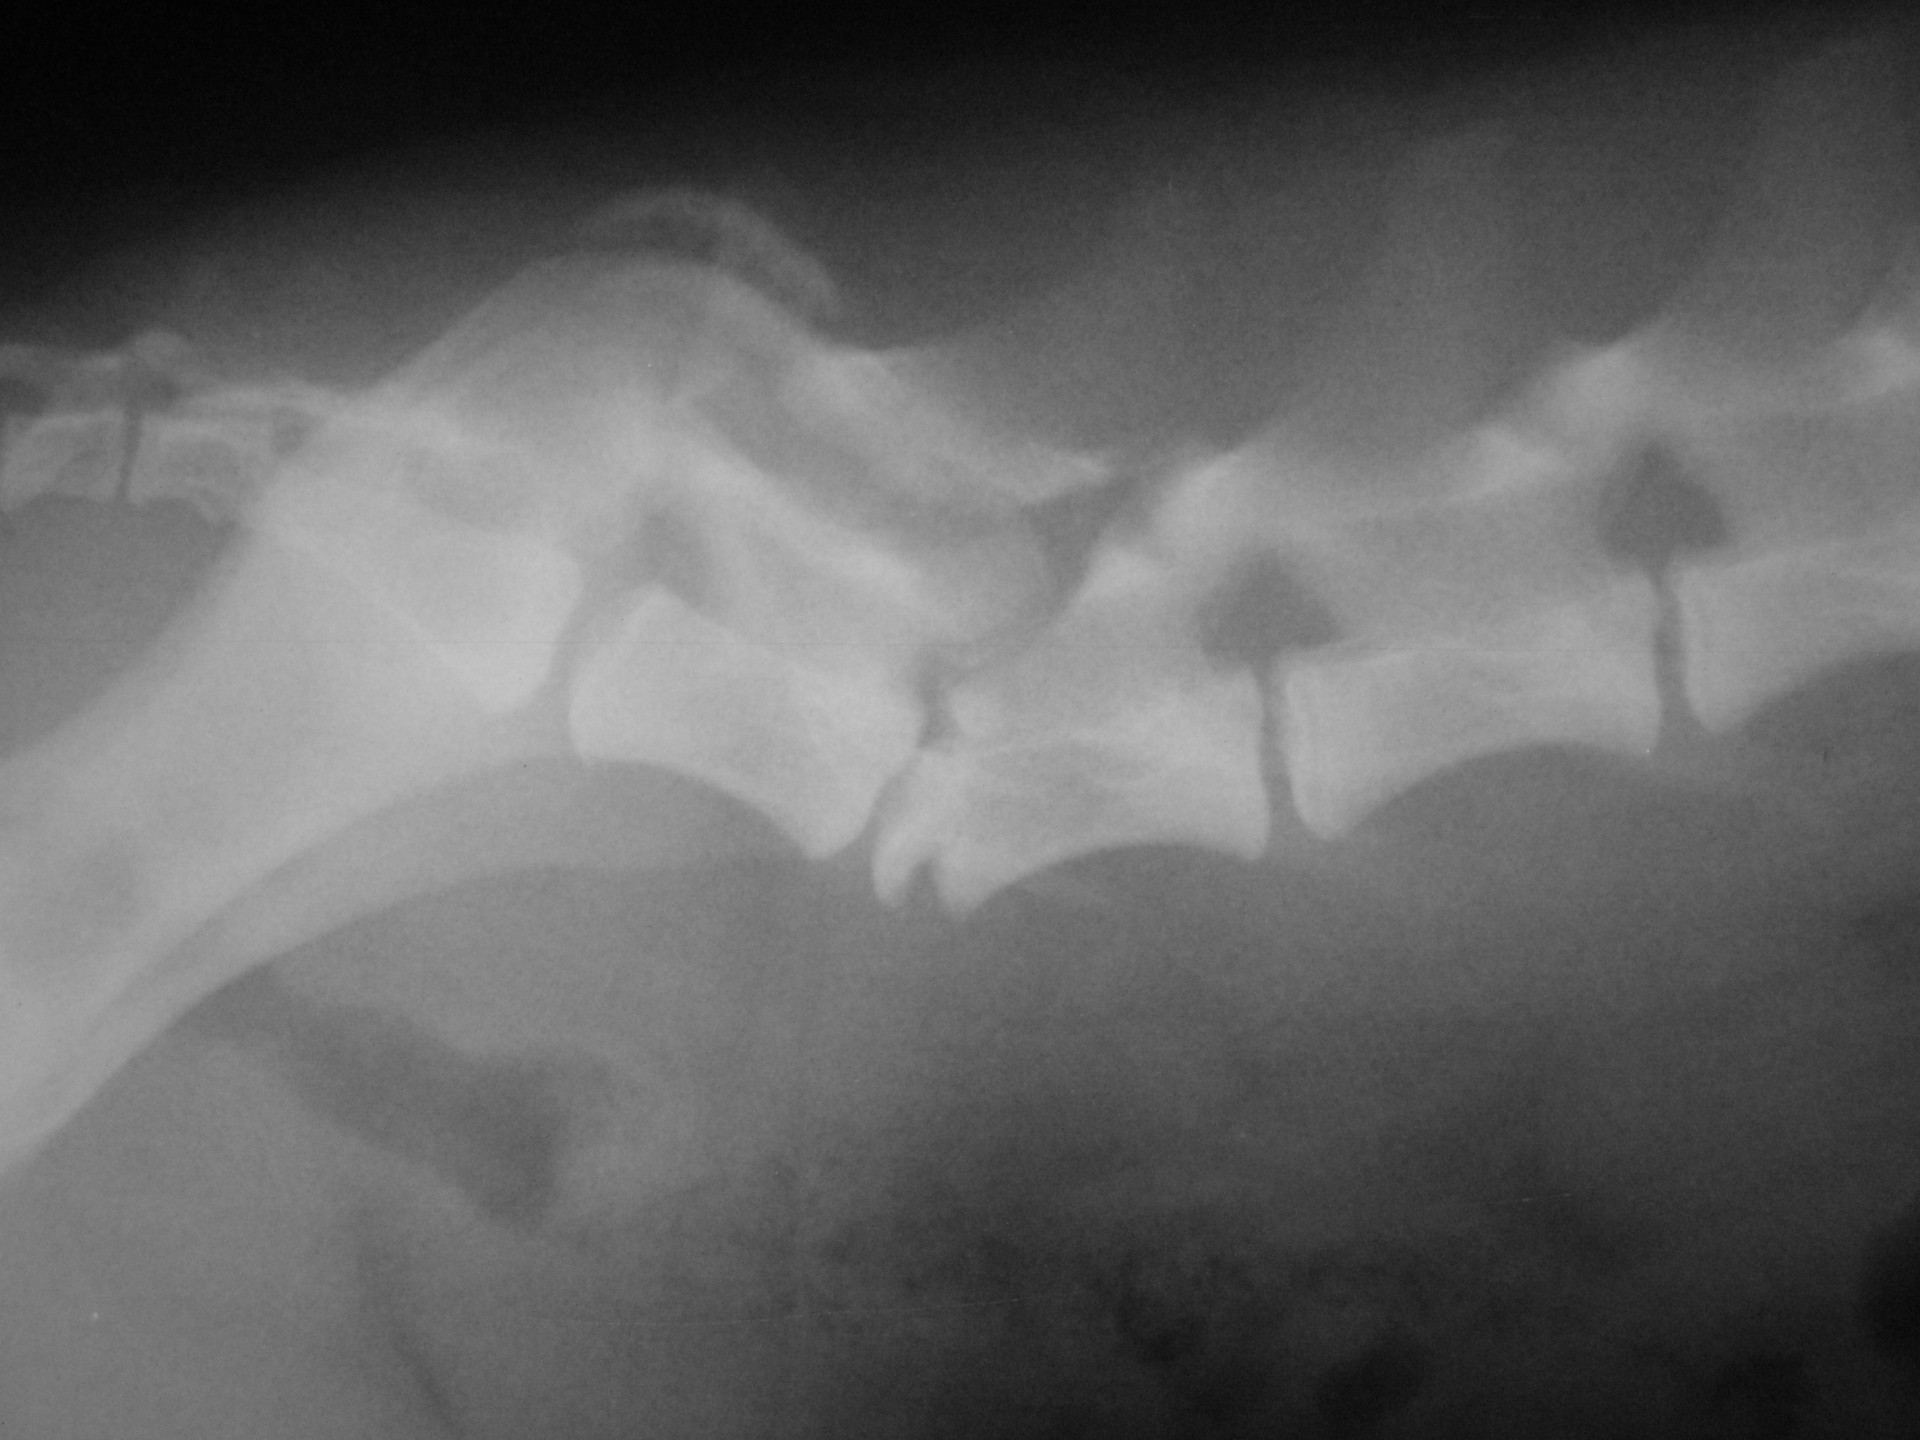

A gerinctörés diagnózisának felállítása komoly döntés elé állítja a tulajdonost és az állatorvost egyaránt. A gerinctörés következtében a gerincvelő minden esetben enyhébb-súlyosabb mértékben sérül. A gerincvelő sérülésének mértékét neurológiai vizsgálattal állapítjuk meg, de a diagnózis felállításához nélkülözhetetlen röntgen felvételről is már információt nyerhetünk a gerincvelő várható állapotáról. A tört végek egymáshoz képest történő kis mértékű elmozdulása esetén a gerincvelő körüli területek bevérzése miatt kialakult neurológiai tünetekkel találkozunk míg nagymértékű elmozdulásuk a gerincvelőt gyakorlatilag olló szerűen elnyírhatja. Így a natív röntgen felvételen a gerinccsatorna elmozdulásából már következtetést vonhatunk le a gerincvelőt ért sérülés mértékéről. A gerincvelő tényleges állapotáról azonban csak neurológiai vizsgálattal győződhetünk meg!

A gerinctörések műtéti ellátása kettős feladatot jelent: egyrészről a törés és elmozdulás következtében kialakult gerincvelő összenyomatást kell megszüntetni, másrészről a tört végeket kell adaptálni és eredeti állapotban - a további elmozdulás megakadályozása érdekében - rögzíteni. A műtéti ellátás során ezért minden esetben az érintett területen a gerinccsatorna felső csontos ívét eltávolítjuk (total laminectomia) így a gerincvelő sérülésének mértéke egyértelműen látható ill. a későbbi összenyomatása elkerülhető.

A törött csigolyatestek adaptációja és rögzítése a nyitott gerinccsatorna mellett komoly kihívást jelent. A későbbi elmozdulás elkerülésére többféle műtéttechnika alkalmazható, melyek közül a csigolyatestek lemezes osteosynthesise ill a fixateur interna használata terjedt el leginkább. Első esetben a sérülés előtti és mögötti csigolyákat lemez és csavarok segítségével egymáshoz rögzítjük, míg az utóbbi esetben a törés előtti és mögötti egy vagy több csigolyatestet két oldalról behelyezett csavarok és egy steril kétkomponensű akrilát műgyanta segítségével rögzítjük.